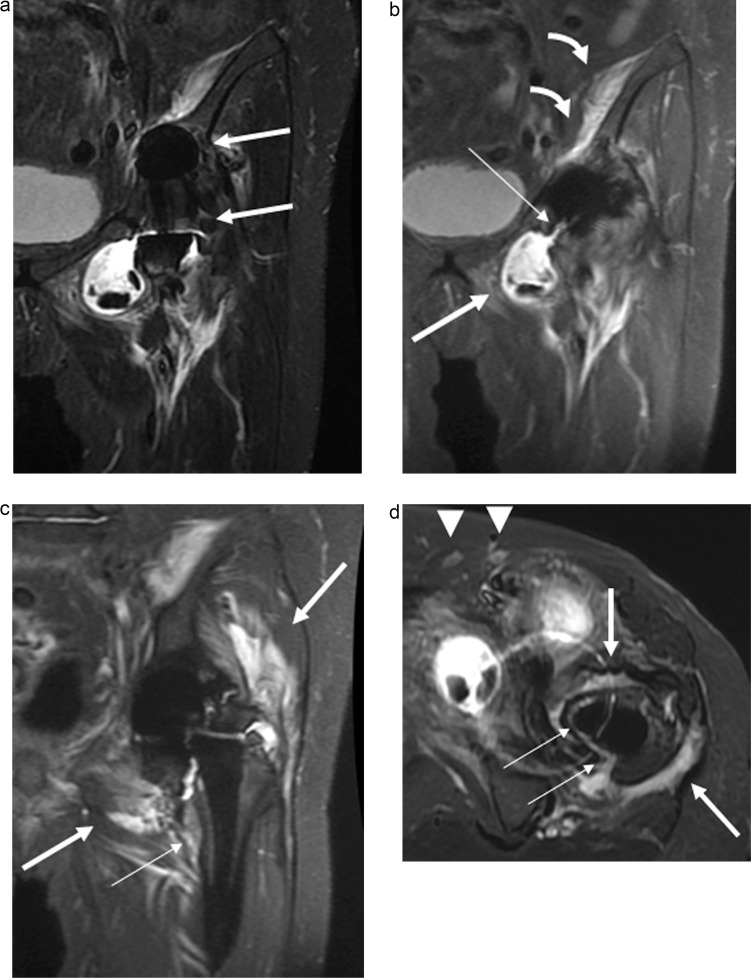

Results: Thirty-seven hip joints in 24 Asian patients (age = 73.9 ± 10.8 years; 18 females) were included. Twelve hip joints (32%) had PJI; seven underwent a surgical intervention. The significant findings for hip PJI included periosteal edema of the acetabulum, intermuscular edema, intramuscular fluid collection, and lymphadenopathy (P < 0.05). In the cases with surgical intervention, the significant findings included capsular distension, capsular thickening, an osteolysis-like pattern of the femur, subcutaneous fluid collection, and lymphadenopathy (P < 0.05). The MRI impressions had high diagnostic significance for both hip PJI cases and those with surgical intervention (P < 0.001). The MRI impression was more significant for hip PJI than the other clinical markers (P < 0.05), while the other clinical markers were more significant in the cases with surgical intervention (P < 0.05).

Conclusion: The significant findings in the hip PJI cases included acetabular periosteal edema, intermuscular edema, intramuscular fluid collection, and lymphadenopathy. The significant findings in the cases with surgical intervention included capsular distention, capsular thickening, a femoral osteolysis-like pattern, subcutaneous fluid collection, and lymphadenopathy. The utilization of MAR MRI demonstrated great diagnostic significance for hip PJI.